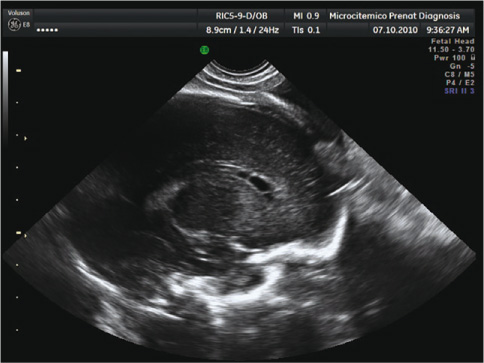

A 35-year-old woman in her first pregnancy had two uneventful ultrasound routine examinations at 12 and 22 weeks. At 28 weeks plus 4 days, she was referred to our unit because of persistent positivity of immunoglobulins M and G against cytomegalovirus (CMV) during pregnancy. Because of the titer stability of immunoglobulins M and G and the high avidity of immunoglobulin G since the early weeks, an infection contracted during pregnancy was considered unlikely. A careful examination of fetal anatomy by transabdominal ultrasound was performed. Fetal transabdominal ultrasound showed normal growth and anatomy. Because of the position being cephalic and the clinical indication, the specific examination of the fetal brain (neuroscan) was performed by transvaginal sonography. By transvaginal bidimensional ultrasound, bilateral tear-shaped cystic structures were detected adjacent to the side wall of the anterior horns of the cerebral ventricles (Figure 1), whose presence was not suspected in the previous transabdominal examination. Through a more detailed study, conducted by sweeping the head volume obtained by three-dimensional ultrasound, the bilaterally symmetrical cystic structures, located in the caudothalamic groove, showed a thin echogenic wall, and were oval-shaped with a maximum diameter of 14 mm and a depth of 5 mm. Some thin septa were present inside the structures, which identified three chambers for each side (Figure 1).

Periventricular pseudocysts detected by transvaginal ultrasound at 28 weeks plus 4 days.

Thin septa are evident, which delimited three chambers for each side.